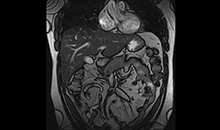

Uygulama Görüntüleri